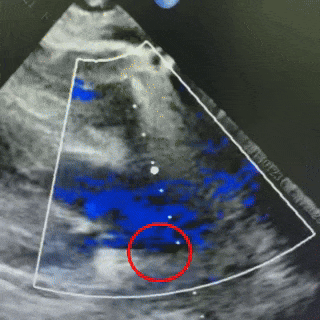

术后3个月随访

可见封堵器形态良好,无残余分流